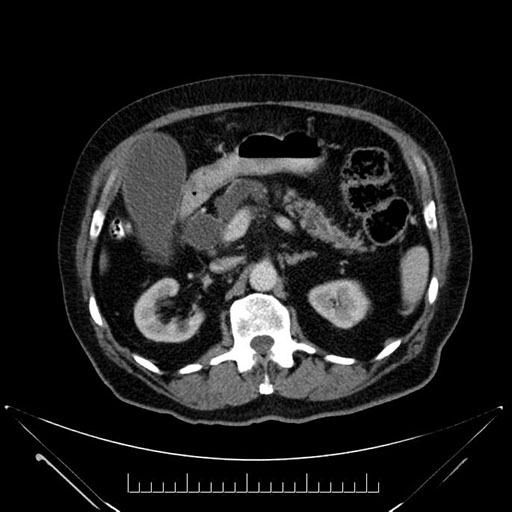

Imaging Analysis

Look through the patient's CT scan to identify any areas of concern for the necessary procedure.

Based on your CT findings, which issue(s) would give reason for "planned slowing down moment(s)" in this case?